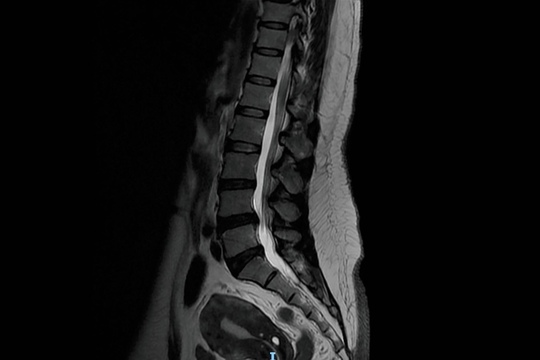

脊柱管狭窄症のMRI画像

脊柱管狭窄症は、背骨の中を通る神経の通り道が狭くなることで、足のしびれや痛み、歩行障害などさまざまな不調を引き起こす疾患です。特に50代以降に多く、日常の姿勢や加齢による変化が大きく関わっています。